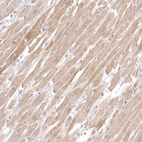

Immunohistochemical staining of human Heart muscle shows moderate cytoplasmic positivity in cardiomyocytes.